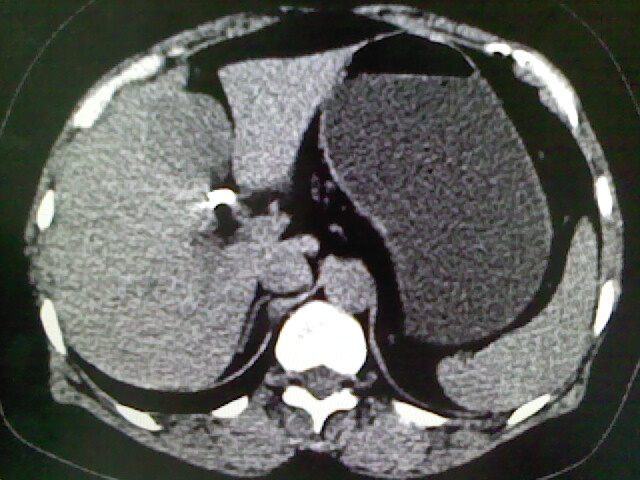

以下是引用卜一在2009-4-2 13:26:00的发言:[br]胆囊颈部结石伴胆囊炎!另:建议增强,待除外肝内占位及胆囊占位!

以下是引用liaoqiang在2009-4-2 16:23:00的发言:[br]胆囊是否切除?胆囊颈区致密影考虑金属夹?结石?肝脏右叶低密度影,考虑增强。